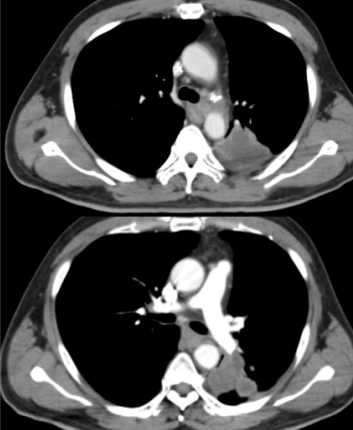

自2024年7月起,由卢冰教授率领贵州医科大学附属医院、附属肿瘤医院胸部肿瘤科团队和放射物理师团队率先开展SFRT的临床应用,至今已完成几十例患者的临床治疗。第1例应用SFRT治疗的患者由卢冰教授带领李青松副主任医师、胡银祥高级工程师完成。对一例LA-NSCLC患者在同期放化疗联合免疫维持治疗的标准治疗模式中,放疗采用SFRT,疗程结束时肿瘤明显缩小,定期随访发现肿瘤完全消失(图示),取得了远超常规放疗的临床效果,而且无明显的放疗并发症,病人生活质量满意,可自行驾车外出游玩。

放疗结束后

1个月CT影像

7个月CT影像